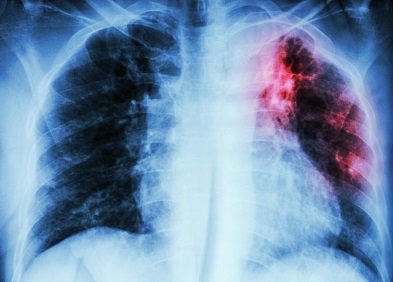

La FPI est une maladie qui attaque le poumon dont le tissu devient épais, rigide et cicatrisé au fil du temps. Elle affecte les personnes de plus de 50 ans et est souvent révélée par des facteurs comme le tabagisme, la pollution de l’air et de l’environnement, la proximité avec certains types d’oiseaux, l’usage excessif des détergents, la Covid-19, etc.

Cette maladie touche entre 14 et 34 individus sur 100.000 habitants au monde et se manifeste, selon le cas, par un essoufflement et une incapacité du reste des organes à recevoir suffisamment oxygène pour fonctionner correctement.